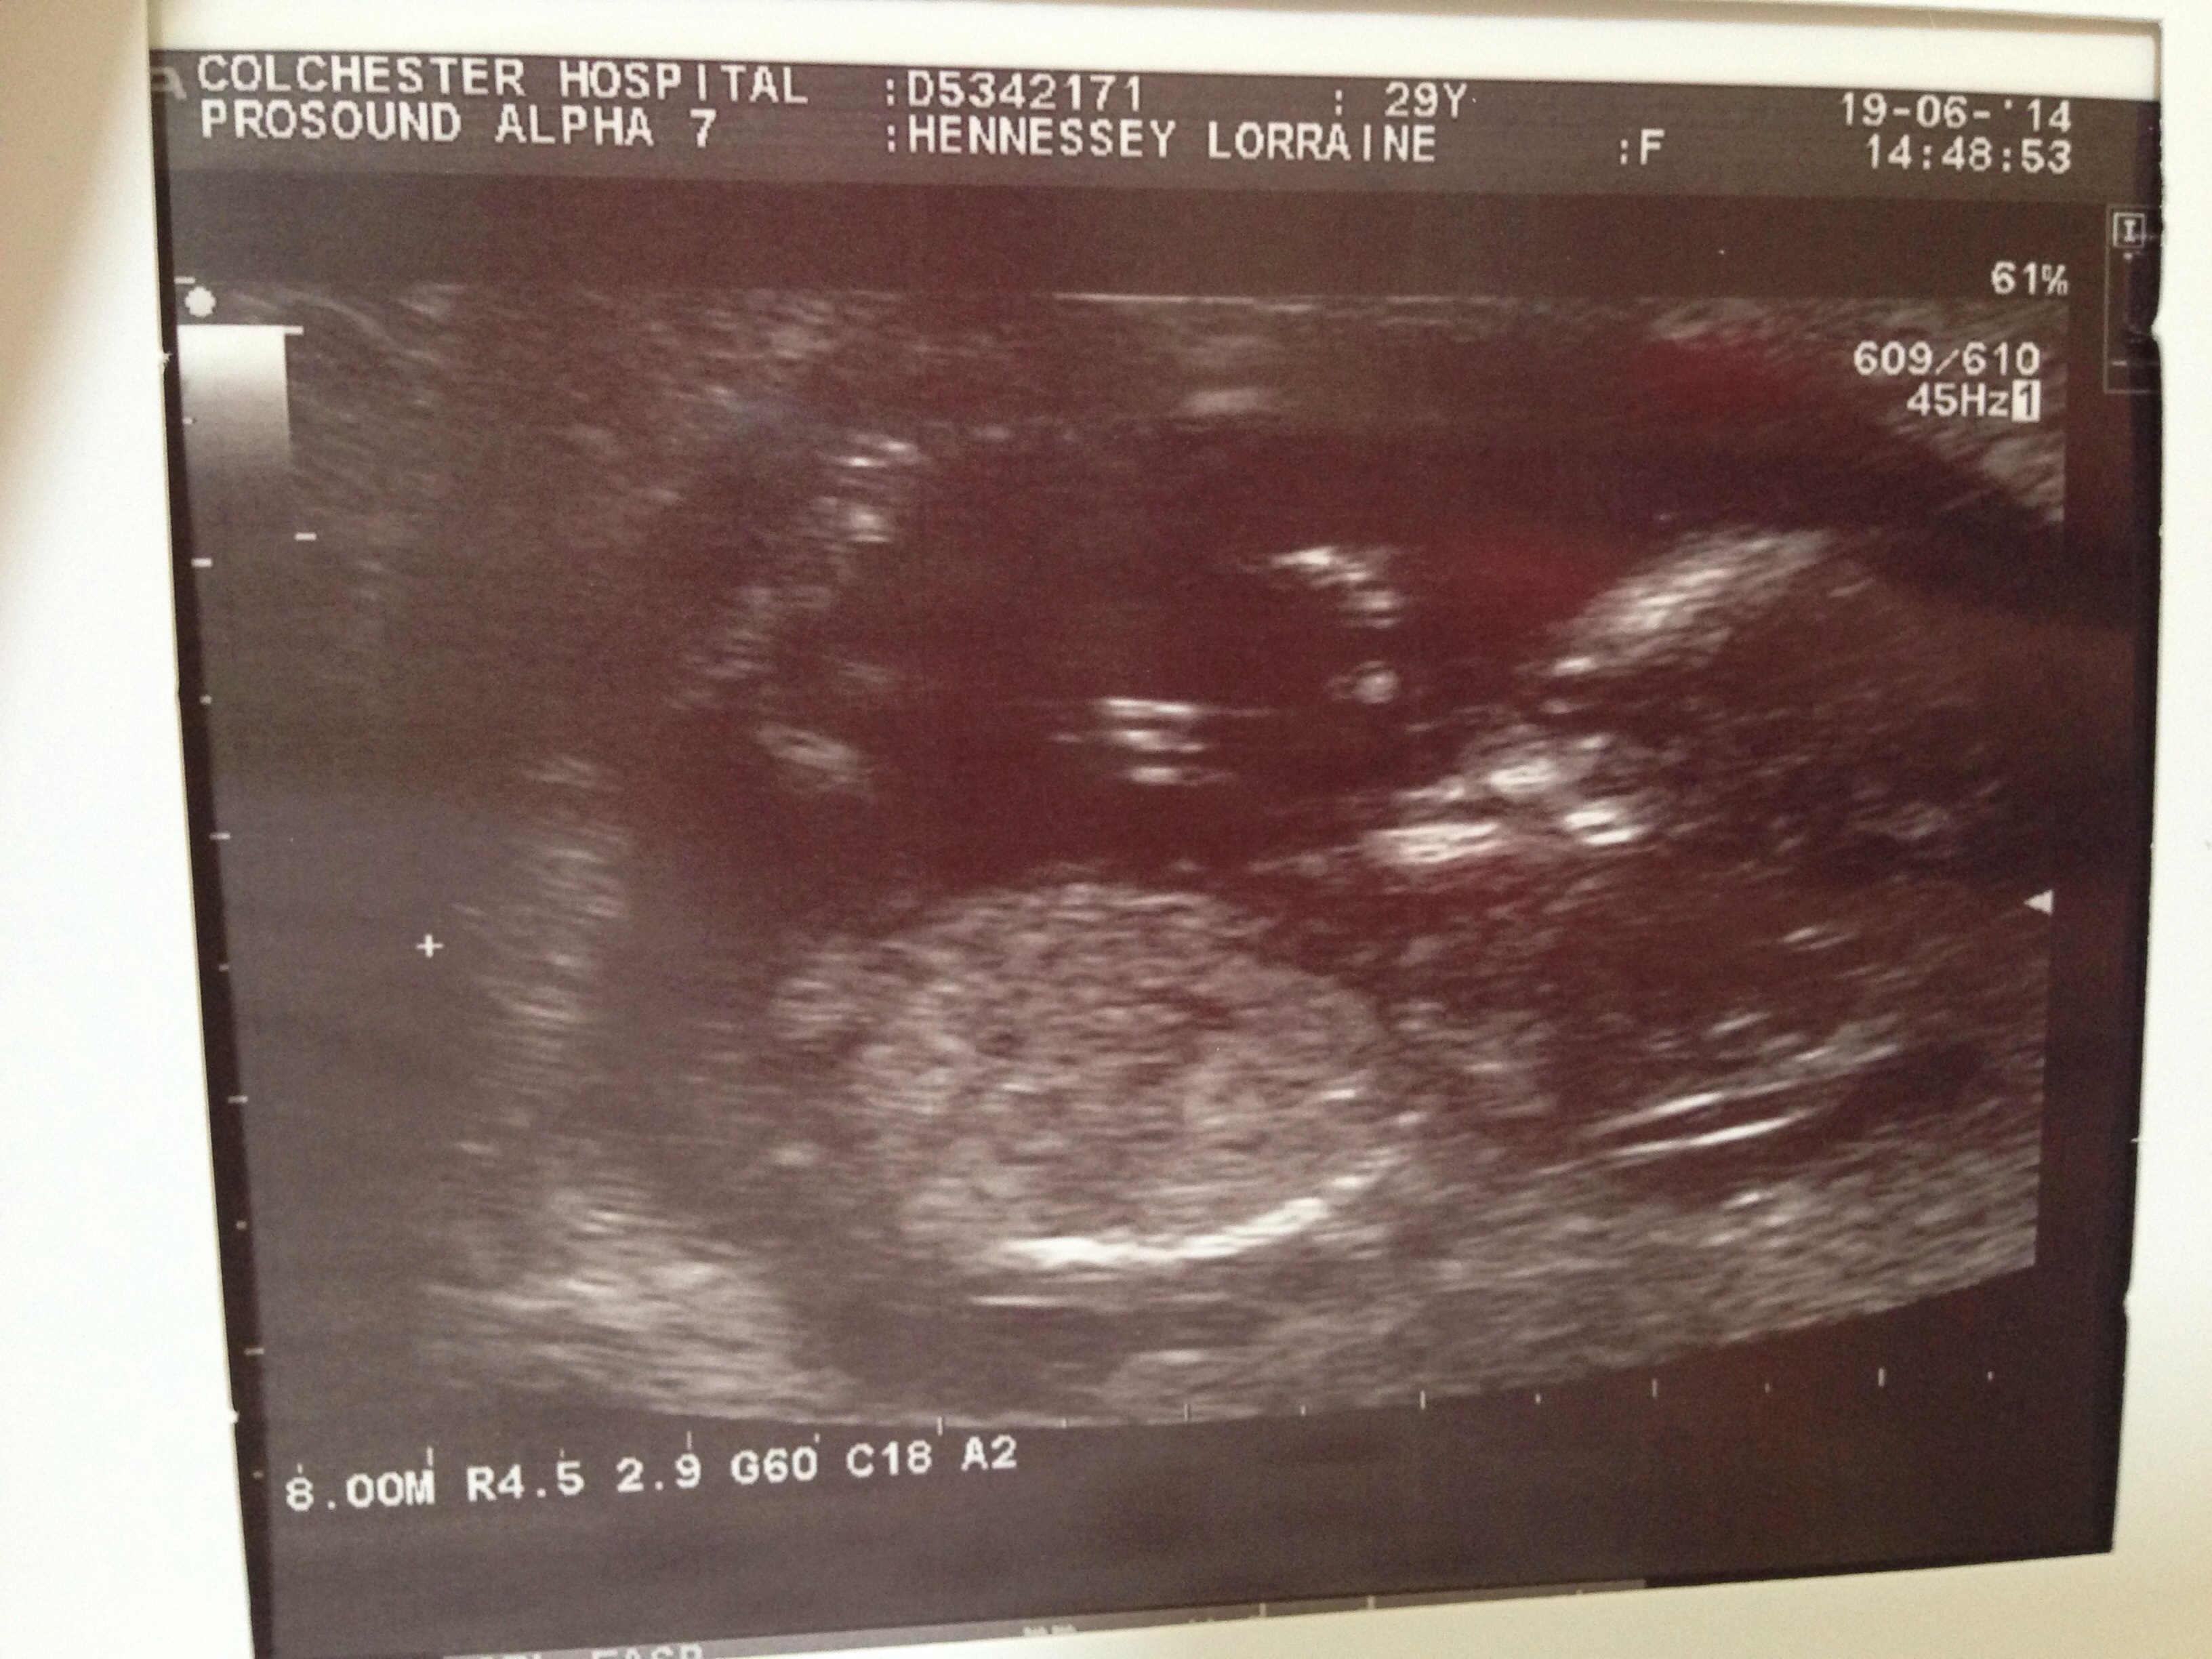

Hi guys. I lost my first little one at 7 weeks (although it measured only 5) in March. We were really fortunate to fall just 2 weeks after the miscarriage but I am terrified of losing this one. We had a scan at 7+5 and saw its tiny heart beating which was AMAZING! But even though I have no reason to suspect anything has gone wrong (apart from some cramping which apparently is normal...?!?) I am terrified that I'm going to go to my scan tomorrow and they tell me he's gone. I'm going crazy, I haven't slept all the way through a night since week 4 but this week has been the worst yet.

• Well, we had our scan yesterday and saw the teeny tiny heart beating. He even did some somersaults and sucked his thumb. He wasn't impressed about being poked so much tho. Lol. Thank you all sooooo much for ur T&P's.

• Burdygirl, I was actually sent off to get candy by the sonographer as he was sleeping upside down on his tummy. Lol. He then started somersaulting! Loved every minute of it. Xx